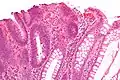

| Трубчатая аденома | Трубчатые железы с удлинёнными ядрами (как минимум незначительная атипия) | Да | ![]() |

|

| Тип полипа | Гистологическое строение | Риск злокачественного развития | Микроснимок[3] | Синдром |

В таблице представлена типология полипов на основе специфики их гистологического строения [1][2]